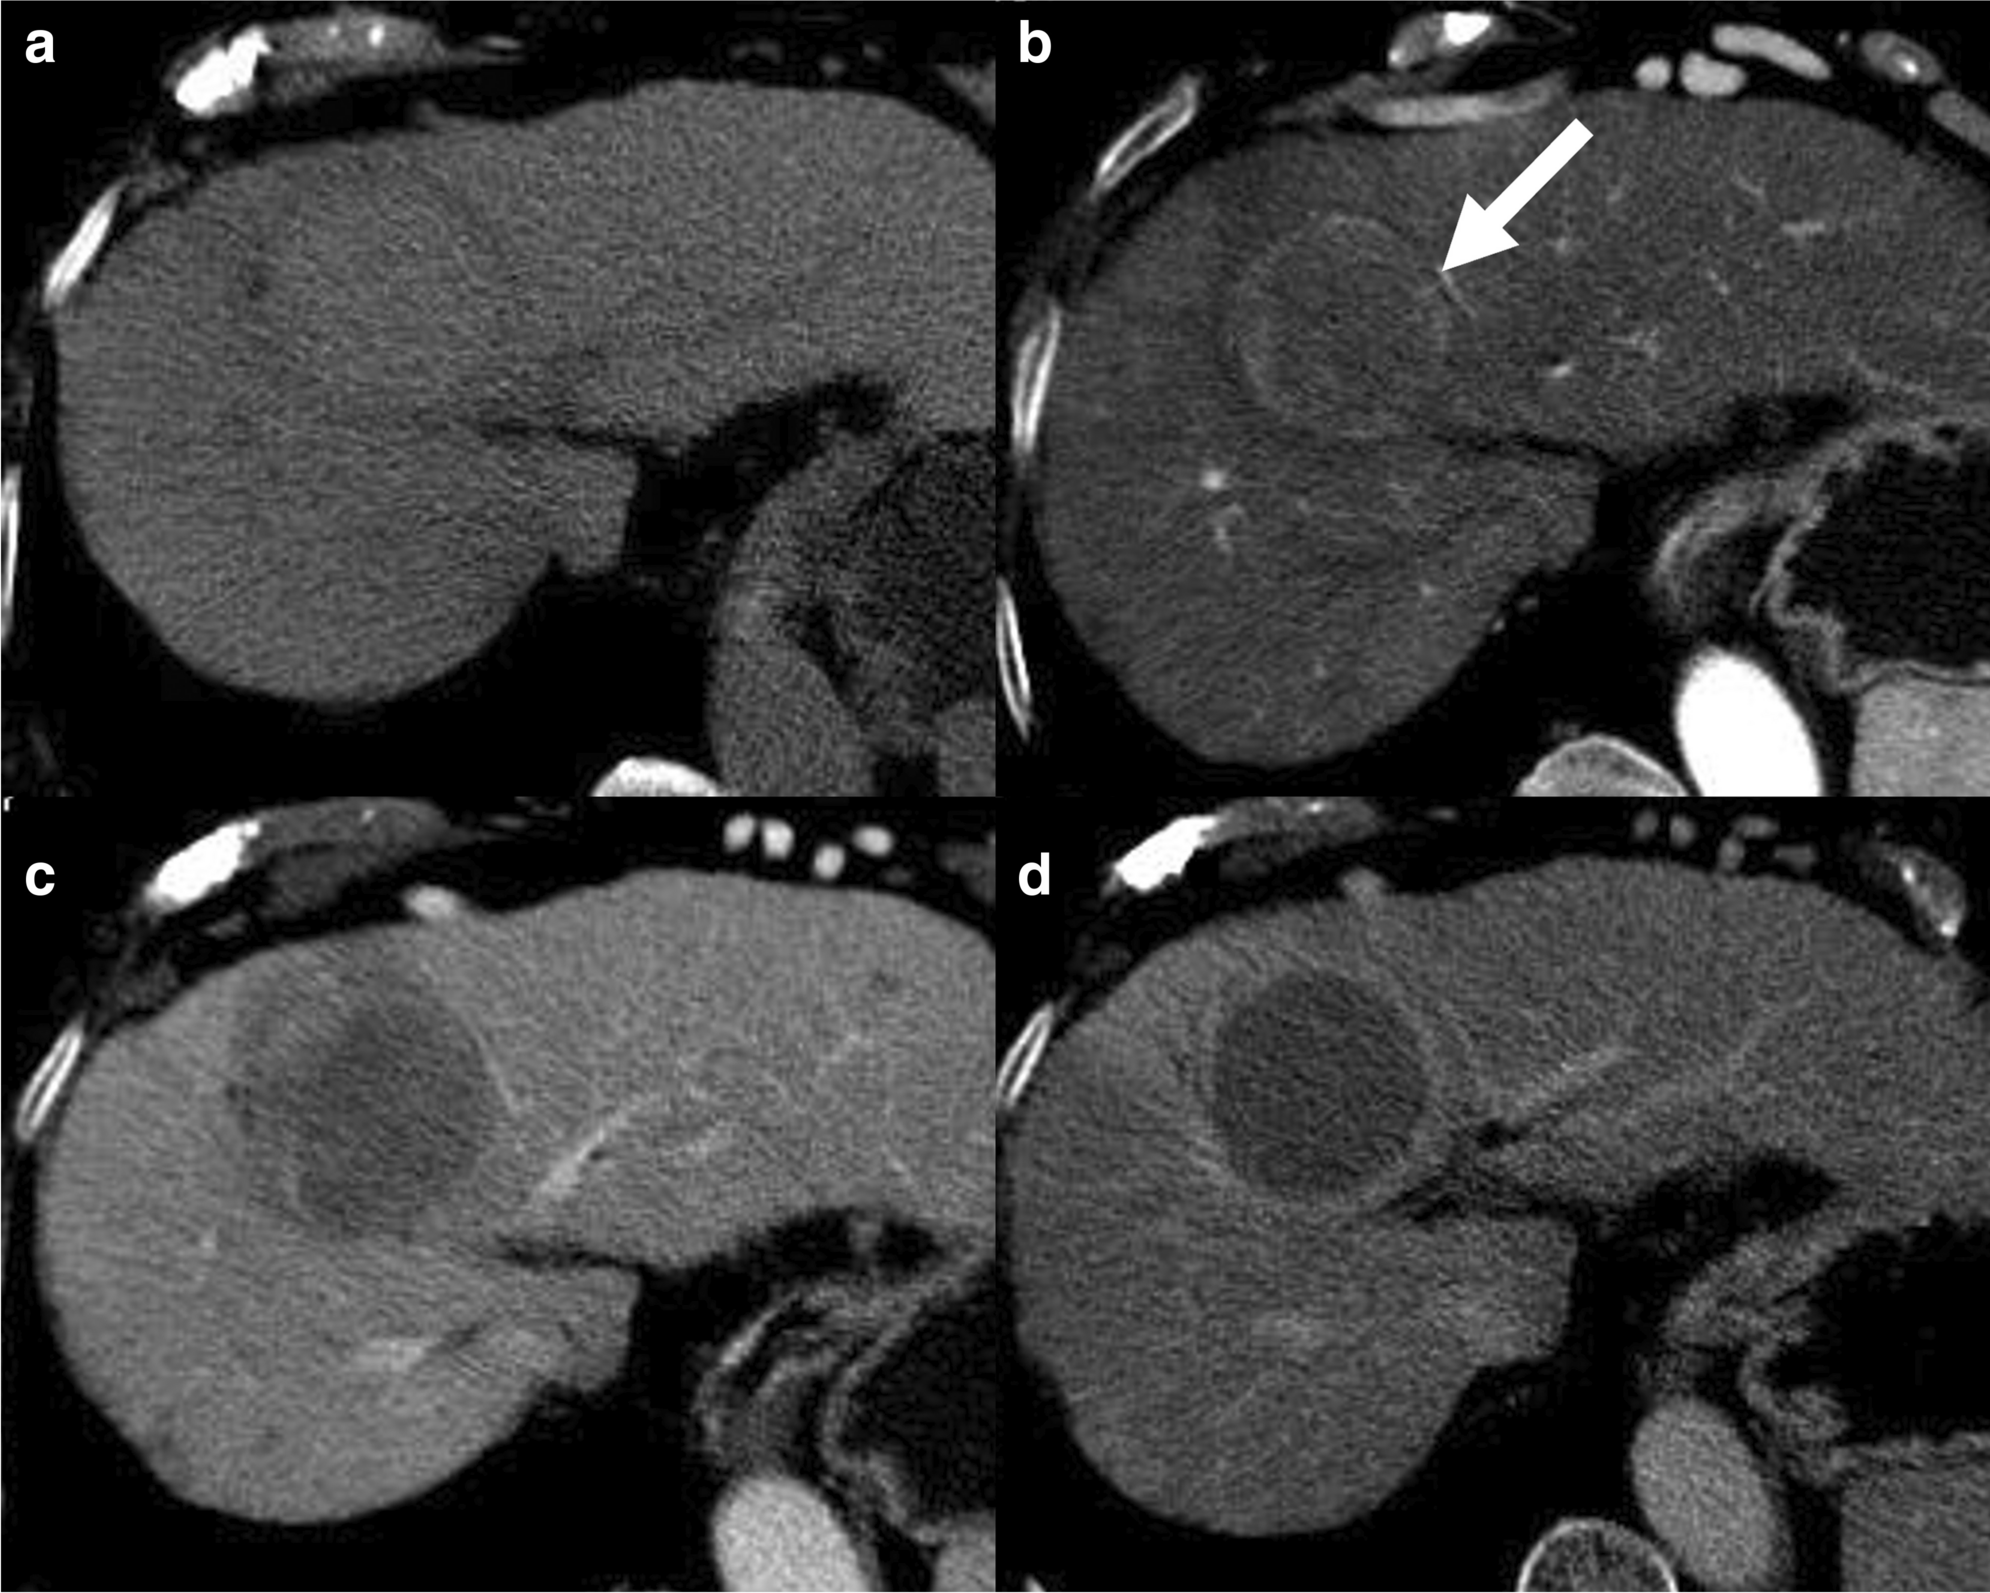

69 M with PMH of HCV cirrhosis & HCC s/p resection in 14 years ago presenting today for a screening ultrasound.

135/73 mmHg / 78 bpm / 16 breaths/min / 96.4°F

sclerae anicteric, no jaundice

CMP wnl, AFP 5